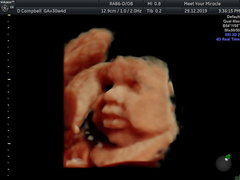

Here's my little fatty. Look at his cheeks and lips 😂😍

March Babies #5

@whiskersonkittenss he's adorable!!! How far gone are you? X

@whiskersonkittenss Omg those are amazing, how clear are those images?! He's so cute! X

@whiskersonkittenss those scan photos are so cute! I had a 3D scan a few weeks ago and I wish I waited a bit longer until baby got a bit chubbier😍